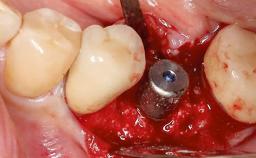

Despite anti-infective surgical treatment, some patients may experience recurrent infection and progressive bone loss requiring additional treatment. This case describes a conservative approach using an implant retrieval tool without the need for excessive bone removal or use of a trephine.

A 65-year-old female patient was referred to the periodontist for assessment and management of infection associated with an implant at site 12. The general dentist had noted suppuration on probing during examination.